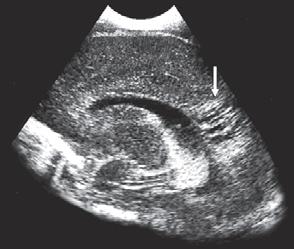

1 7 4 Vrozená brániční kýla 18

1 7 .5 Neonatální pneumonie . . . . .